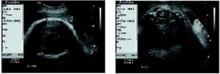

• Ultrasound measurements. Since estimates of fetal weight have a margin of error approaching 40%,9 others have chosen different parameters for determining fetal macrosomia in women with diabetes. In a retrospective study involving 31 women with gestational diabetes, Cohen et al22 found that subtracting the fetal biparietal diameter from the abdominal diameter—with both measurements obtained via ultrasound—yields a predictability score higher than estimated fetal weight. Specifically, if the difference between the 2 measurements is 2.6 cm or more, the rate of shoulder dystocia is high enough to warrant elective cesarean (FIGURE ).

FIGURE Using ultrasound measurements to predict macrosomia

A simple way to predict fetal macrosomia in women with diabetes is to subtract the fetal biparietal diameter (9.3 cm in the scan at left) from the abdominal diameter (average of 12.44 cm in the scan at right). If the difference exceeds 2.6 cm, elective cesarean is warranted. In this case it is 3.14 cm, indicating elective cesarean is warranted.